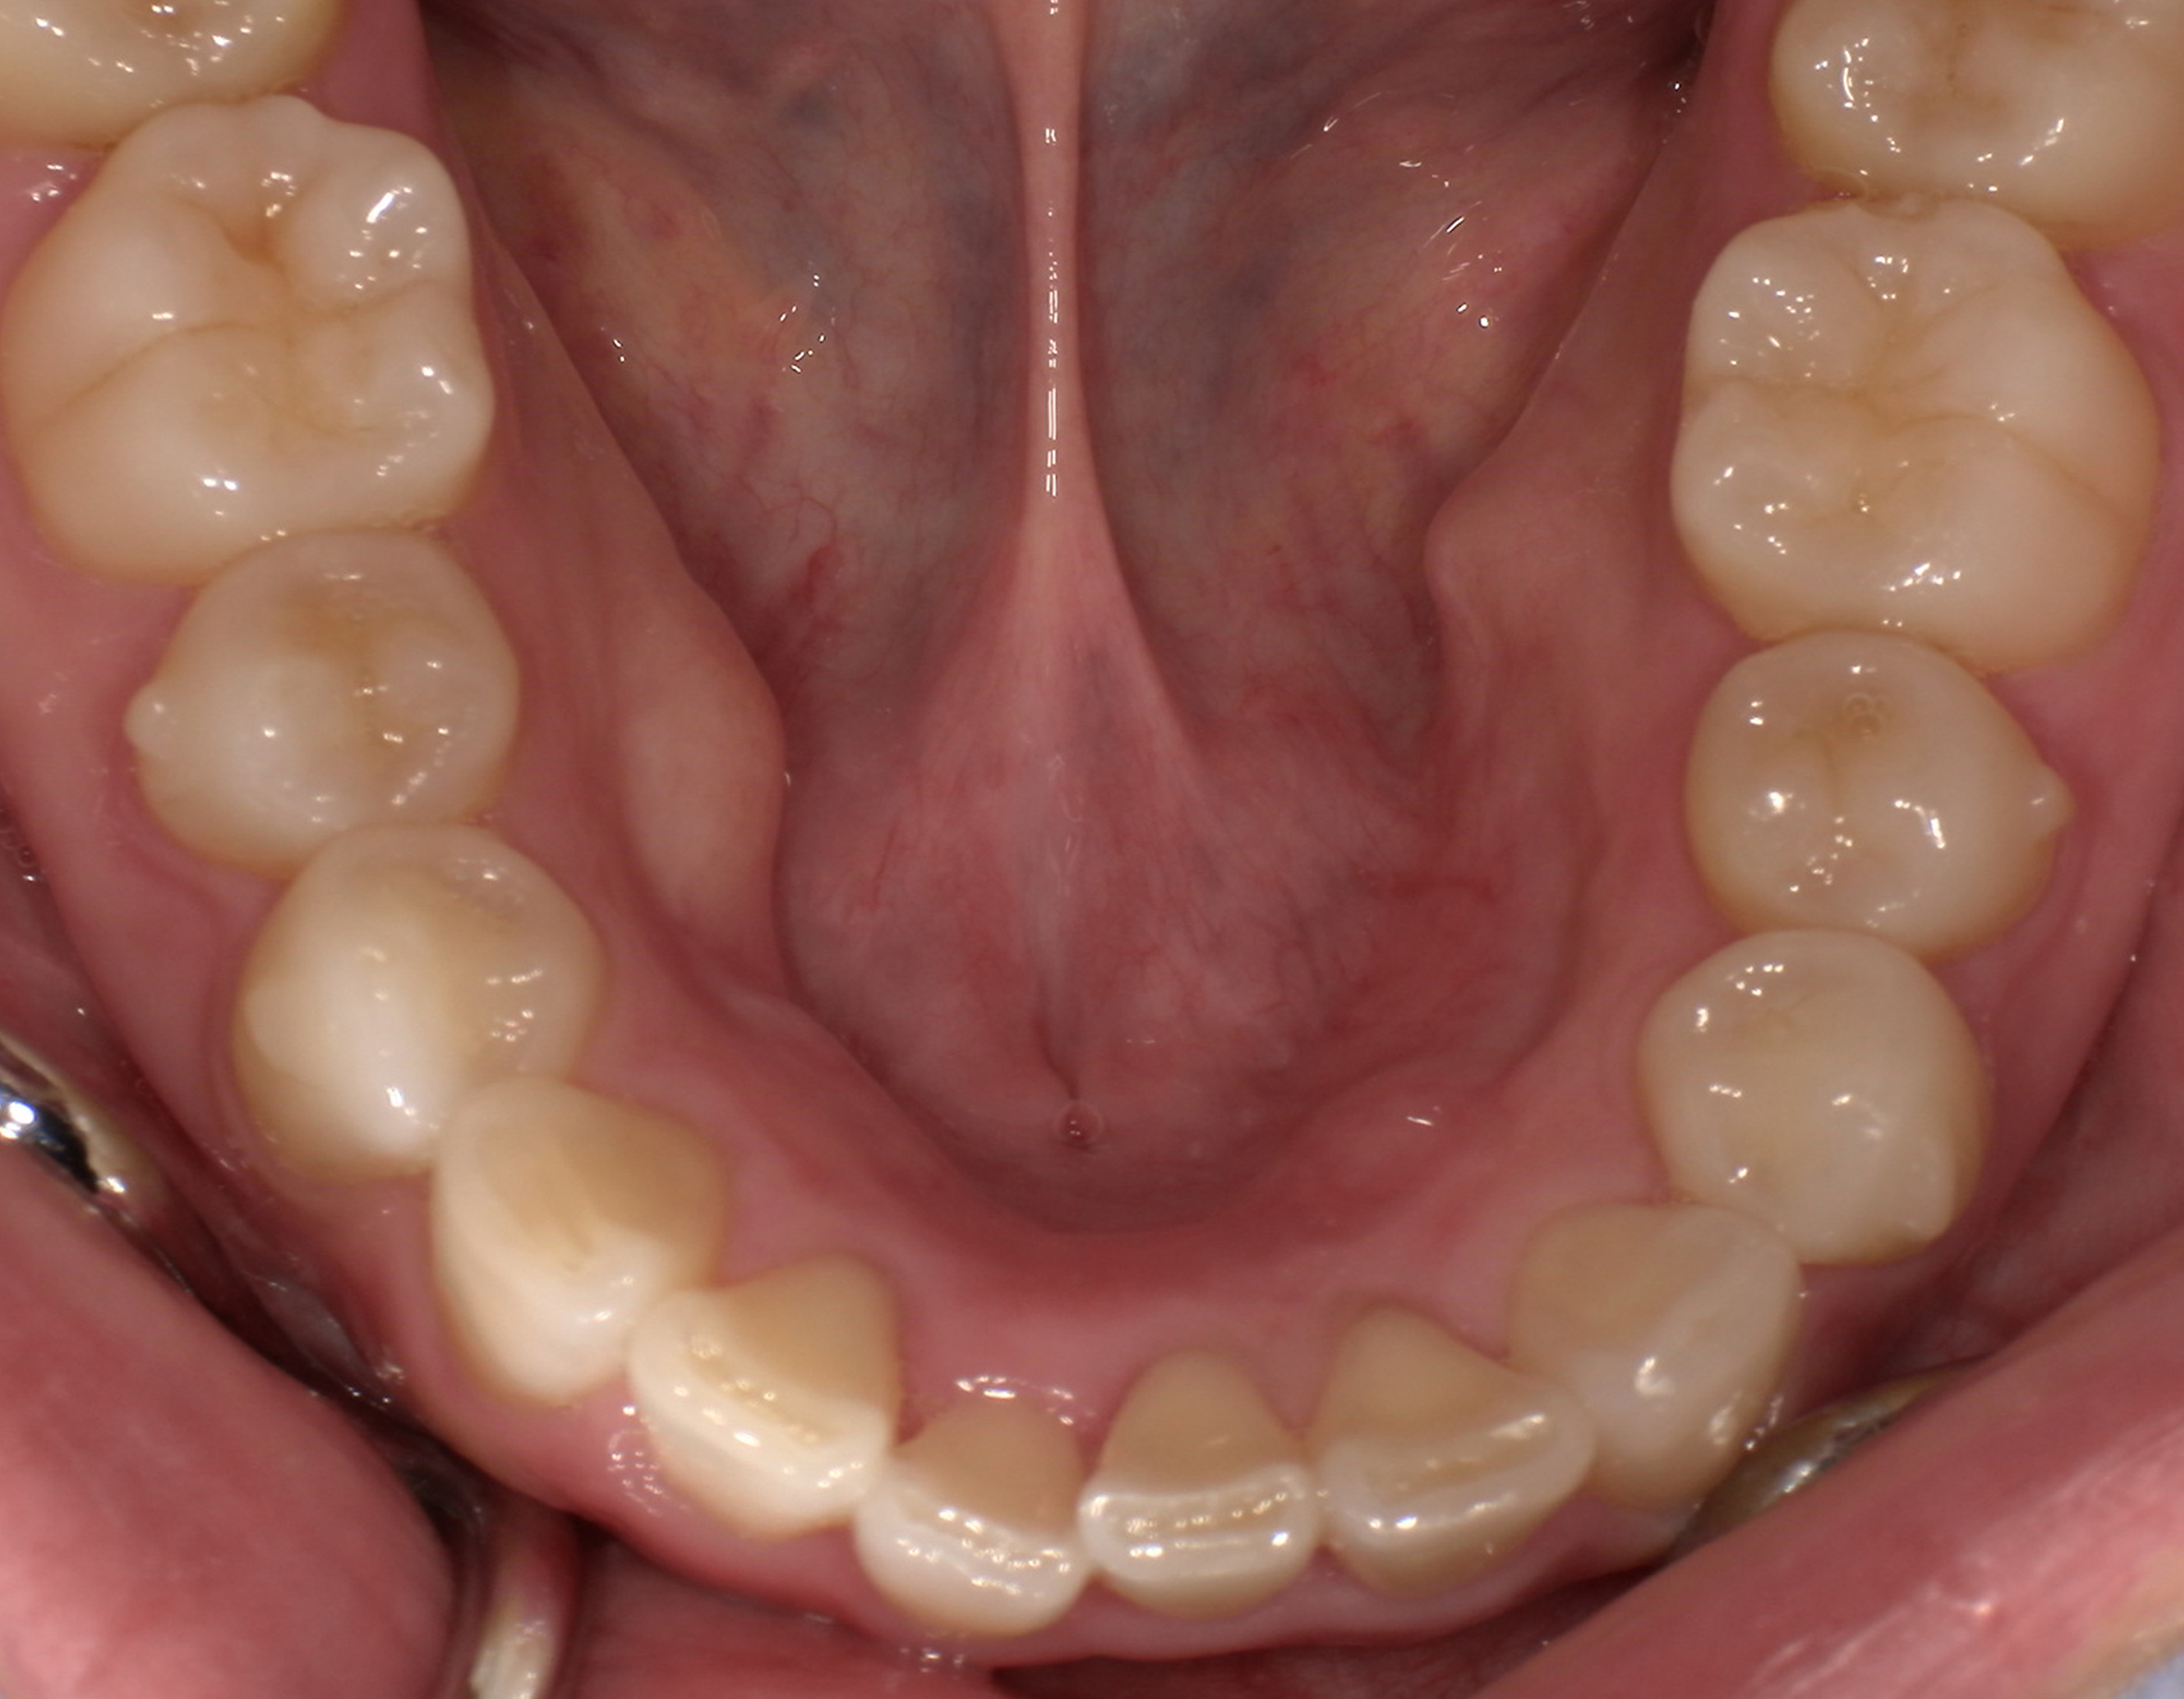

術前・術後の比較

| 術前 | 術後 |

|---|---|

![]() ![]() |

治療の経過を表示する

親知らずの痛みがなくなった患者さんは、昔から歯並びが気になっていることを打ち明けてくれました。特に上の歯が少し前に出ていたり、隙間があったりしている点を治したいそうです。そこで、まず上の歯並びの矯正治療を開始しました。

最初のお口の中 ワイヤー装着して治療を開始

-

治療開始後3ヵ月経過すると、前歯の隙間や全体の乱れが減ってきました。口笛が吹けるようになったとのことです。

最初のお口の中 治療開始3ヵ月後

6ヵ月経過すると、矯正治療を終了し、前歯に被せ物の治療を行いました。

最初のお口の中 2025/3/22

被せ物装着

当院では、歯並びが気になる人に対して、矯正治療を行っています。また今回の症例のようにワイヤーを用いた治療からマウスピース矯正治療も行っておりますので、スタッフにお声かけください。

治療の概要

| 患者属性 | 30代男性、歯科恐怖症 |

| 主訴 | 上の前歯の歯並びを整えたい |

| 診断 | 歯列不正、う蝕歯 |

| 矯正装置 | 矯正ブラケットとワイヤー |

| 治療期間 | 約6ヵ月 |

| 通院回数 | 8回 |

| 治療費 | 矯正:基本料金(220,000円)+調整料(5,500円×6回)、補綴治療:72,600円、費用は税込 |

| 治療内容 | 上顎側切歯を2本抜歯した後、上顎の歯にブラケットを装着し、ワイヤー、矯正用ゴムで歯の移動を行いました。その後、被せ物の治療を行って治療を終了しています。 |

| リスクと副作用 | 矯正治療

補綴治療

|